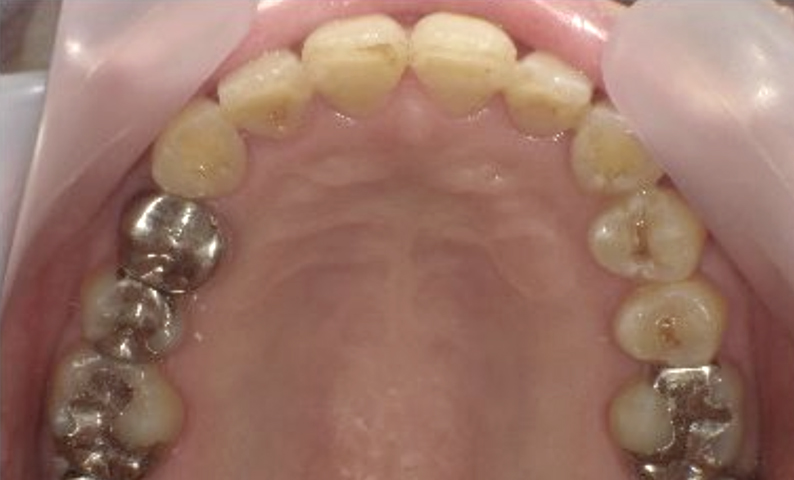

症例_003 下顎だけの部分矯正

治療期間:10ヶ月金額:24万円+税女性前歯のガタガタ下の前歯だけ上顎は補綴治療中

| Before | After |